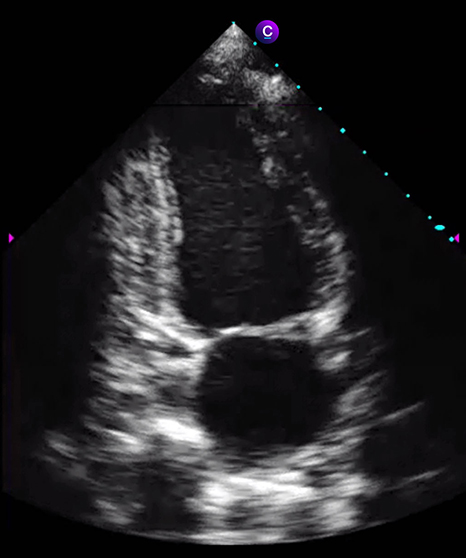

Программное обеспечение Caption Guidance предназначено для использования при проведении двухмерной трансторакальной эхокардиографии у взрослых пациентов, в частности, для получения изображений сердца под разными углами. Эти снимки обычно используют при диагностике заболеваний сердца.